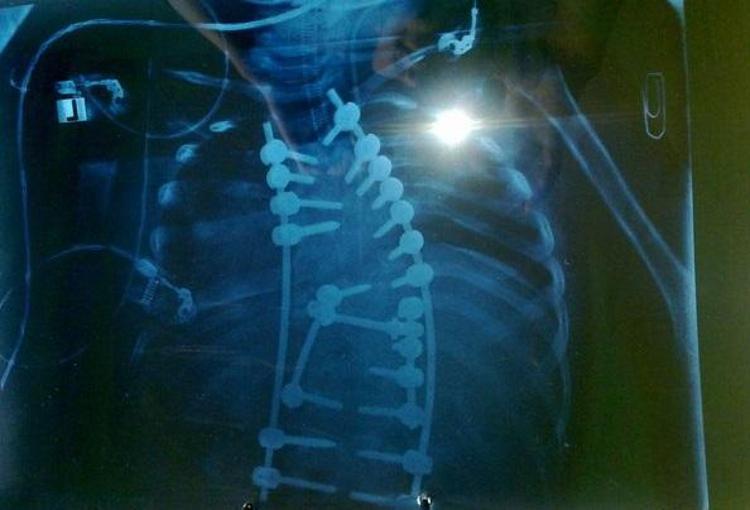

'SOL TARAFINDAKİ OMURGALARININ YÜZDE 70'İ YOK'

Diğer 3 çocuğunun sağlıklı olduğunu, Yücehan'ın hastalığının ise doğuştan kaynaklandığını belirten Kermen, "Yücehan spina bifidalı. Omurilik ve omurga hastalığı. Spina bifida artı skolyoz. Bunlar ikisi de doğumsal anamoli.Sonradan olma skolyozlar var; onlardan değil. Sol tarafındaki omurgalarının yüzde 70'i yok. Spina bifida rahatsızlığından dolayı da rektum ve mesane kontrolü yok. Sol tarafında, sol bacağında kas ve sinir zafiyeti var. Bunlar spina bifida rahatsızlığına bağlı hastalıklar. Skolyoz hastalığına bağlı rahatsızlıkları da yürüme zorluğu ve vücudunun istediği kadar gelişememesi, yaşıtları kadar olamaması" dedi.

Yücehan'ın bugüne kadar 30 ameliyat olduğunu söyleyen Kermen, "İlk omurilik ameliyatını, İstanbul'daki özel hastanede ünlü bir doktor yaptı. Tekrar skolyoz ameliyatları olması gerekiyor. Çünkü Yücehan'ın skolyozu doğduğunda zaten çok ileri dereceydi. C harfi gibiydi vücudu. Yücehan, küçüklü büyüklü 30 ameliyat oldu. İlk ameliyatı 24 saat sürdü. Sonraki süreçlerde artık saymayı bıraktım" ifadelerini kullandı. Pembe Kermen, olması gerekten son ameliyatı ertelendiklerini belirterek, şöyle dedi:"Son bir ameliyat daha olması gerekiyor. Buna, vizyon ameliyatı deniyor. En son gittiğimizde doktorumuza, okulların kapanmasına, sınava 2 ay vardı. Dedi ki; Hocam, ameliyat olursam ne kadar sürede iyileşirim? Hoca da 'En iyi ihtimalle 3 ay' dedi. 'O zaman olmuyorum. Çünkü bu sene liseye başlayacağım. Ve lisenin ilk gününde okula gitmek isterim' dedi. Yücehan, şu anda kendi isteğiyle ameliyatını erteledi."